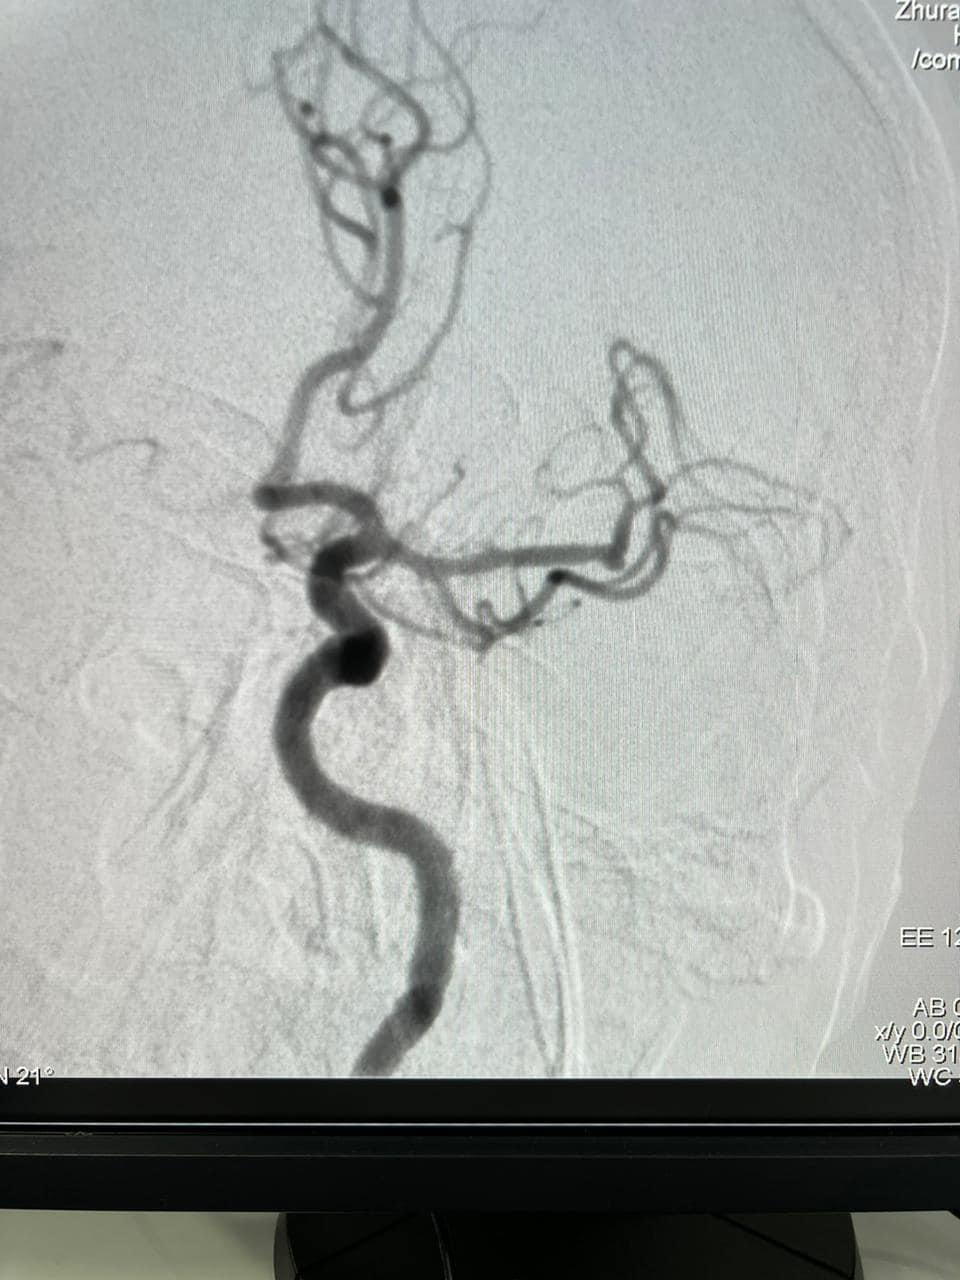

Вперше у Тернопільській області медики нейрохірургічного відділення Тернопільської обласної психоневрологічної лікарні виконали операцію — тромбектомію з дрібних гілок лівої середньої мозкової артерії.

Пацієнт був доставлений до реанімаційного відділення ургентно. При поступленні у нього була відсутня мова та не рухалися праві кінцівки. При КТ-ангіографії був виявлений тромбоз лобної гілки лівої середньої мозкової артерії.

Спочатку лікарі зробили тромболізис, після якої у хворого відновилися рухи у правій руці та частково мова. Лікарі прийняли рішення виконати тромбектомію.

В результаті операції у хворого вдалося відкрити велику гілку лівої середньої мозкової артерії та відновити кровообіг по більшості судин басейну.

Операцію провели лікарі-інтервенціоналіст Гаджальський В.В., асистент Журавльов О.Ф., анестезіолог Мусієнко А.М., під керівництвом завідувача нейрохірургічним відділенням, лікаря з 20-ти річним стажем роботи у Херсоні — Олексія Леонтьєва.